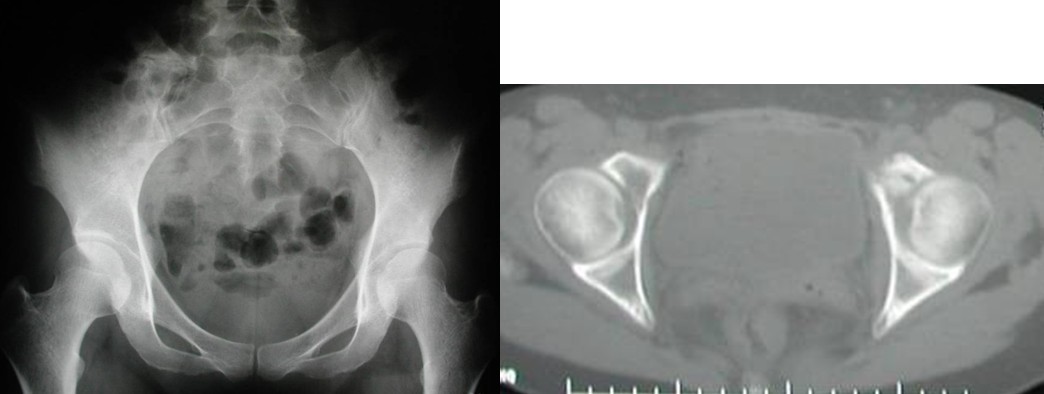

图4,女,52岁,乳腺癌髋臼转移, Harrington III型

Ⅲ型:髋臼内壁、顶部及外侧壁均破坏。仅使用带翼网杯的全髋假体是不够的。在这种情况下,需要在骨盆缺损处放置数根斯氏针以便于将位于解剖位置的髋臼假体所承受的应力传导至脊柱(1-3)。在大多数髋臼周围破坏广泛的病例,需要采用扩大的髂股骨切口入路,以便于探查骨盆内外侧区域。在显露清楚后,自髋臼缺损处沿残留的正常髂骨向骶髂关节方向钻入2-3根斯氏针,并越过关节达到骶骨。应采用较粗的斯氏针,术中还需要X线监测以保证斯氏针的位置。在钻入斯氏针的同时,应用手指触摸坐骨切迹,以保证斯氏针的方向,防止其穿入骨盆内壁。当髋臼缺损较大时,还可以自前部髂嵴向前柱的耻骨及后柱的坐骨钻入更多的斯氏针做进一步的加强。在髋臼假体顶部切断斯氏针,并安装带翼网杯,在髋臼深部可以用金属钛网加强骨水泥固定。术后病人可全部负重行走,但需置患肢外展中立位约4周时间以防止脱位。也有采用马鞍式假体置换的报道, Benevenia等对20例髋臼III型转移瘤患者进行了马鞍假体置换,术后MSTS 93评分平均16.6分,多数病人可以扶拐行走(5)。对于髋臼上壁及内、外侧壁均破坏的HarringtonIII型患者,本组病例中,有7例患者采用了肿瘤刮除后、于骶髂关节处植入3-4枚斯氏针, 骨水泥填充髋臼上壁骨缺损,水泥型全髋重建髋关节。其中,有2例患者出现下地后髋部痛疼,负重时髋部不稳定。考虑为负重时骶骨内斯氏针承受较大剪力, 出现髋关节不稳。因此,在本组病例中,我们对4例Ⅲ型患者实施了整块切除、可调式人工半骨盆置换术。术后6周患者可以扶拐下地行走。平均MSTS93评分为23.3分。